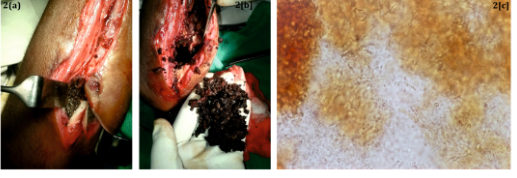

The patient was a young boy of 8years age who hailed from Siddharthnagar area of Uttar Pradesh state in India. He presented with pain, swelling and draining sinus in the right forearm for 4months. He had history of fever for 2months. He also gave a history of trauma to the forearm one year back with breach of skin and probably abscess formation which was treated with incision and drainage at his native place. The patient was symptomless for about 8months. Thereafter he developed swelling over the forearm and there were no external signs of inflammation. Local examination showed tenderness, swelling and a seropurulent discharge from a sinus at the drainage site. The supination-pronation movement of the forearm was greatly restricted. General examination did not reveal any abnormality. Hematological investigations revealed mild leukocytosis (WBC count 15000/mm3) and raised ESR (60mm at the end of 1hour). Other haematological parameters were within normal limits. Ray of the forearm revealed extensive bone destruction (Figure1A). The ultrasonography was suggestive of Infective osteomyelitis with a collection of 3.7x4.7cm. The MRI study showed soft tissue collections in proximal forearm between radius and ulna (Figure 1B).The patient then underwent surgical exploration which revealed cavity between radius and ulna which was full of a black mass. The mass was composed of abundant black grains which may have been discharged in the bony cavity from the surrounding soft tissues. The cavity was further being expanded by the growing mass of fungal grains. Black grains were also observed interspersed in the surrounding tissue. (Figures 2A) (Figure 2B). The debrided material was received for fungal culture. When observed in 10% potassium hydroxide, it showed plentiful brown cementing material interspersed with fungal hyphae (Figure 2C). On culture, a slow growing mould was observed on Sabouraud’s dextrose agar at both 260C and 370C, which was tan at first becoming brownish later. A diffusible brown pigment was observed in the agar and the fungus was identified as Madurella mycetomatis (Figures 3A) (Figure 3B).1

Figure 2 A. Intra operative view of the collection of black grains between the bones

B. Black grains debrided from the tissues.

C. The grains observed microscopically in 10% KOH. Few fungal hyphae embedded in abundant brown cementing amorphous material. X100.